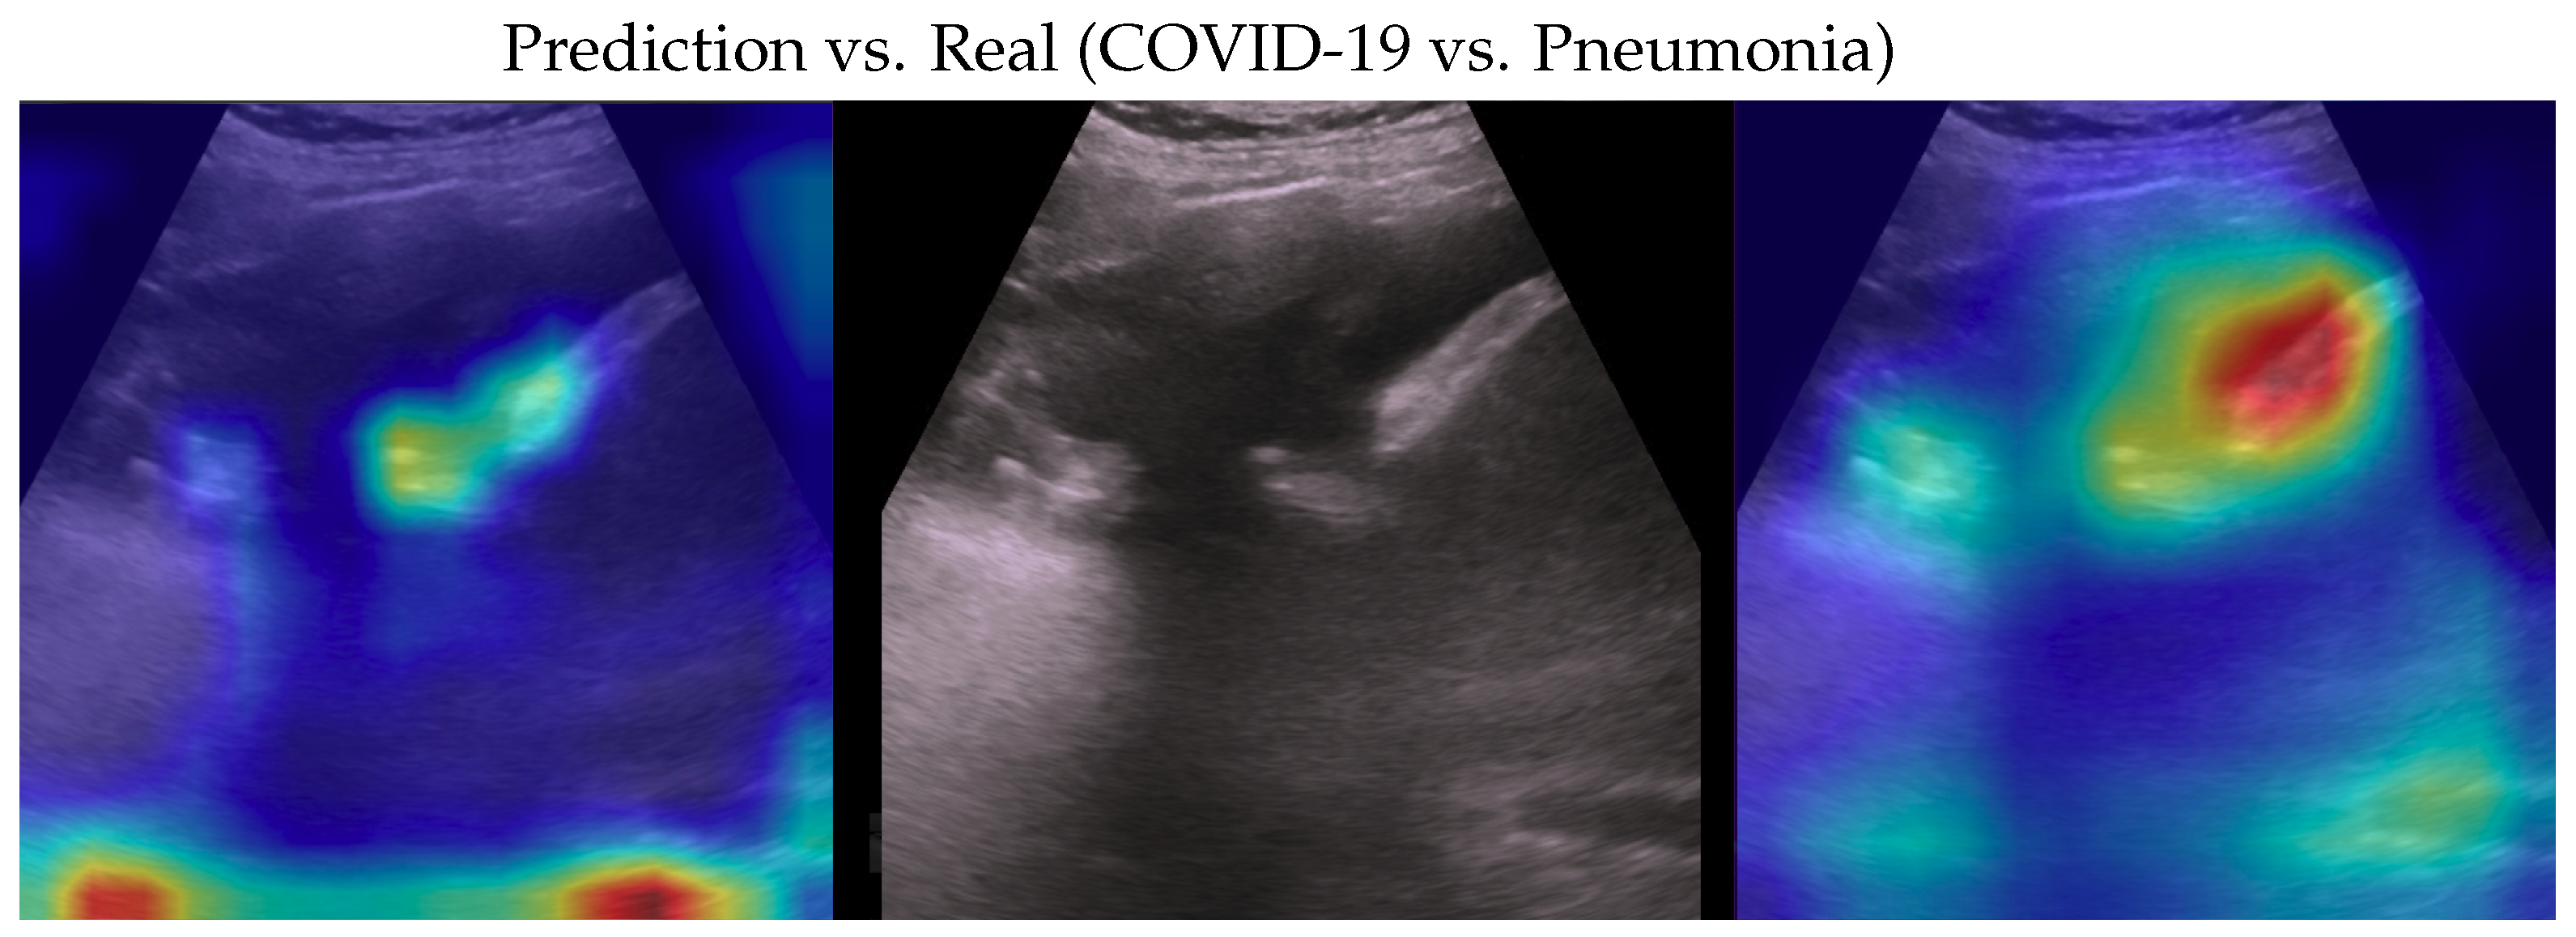

Figure 5. Classification of a COVID-19 image: in the middle, the input image; on the left, the focus of a wrong classification as pneumonia; on the right, the focus of the correct classification obtained by the classifier achieving 100% accuracy. Red (higher) to blue (lower) scale.